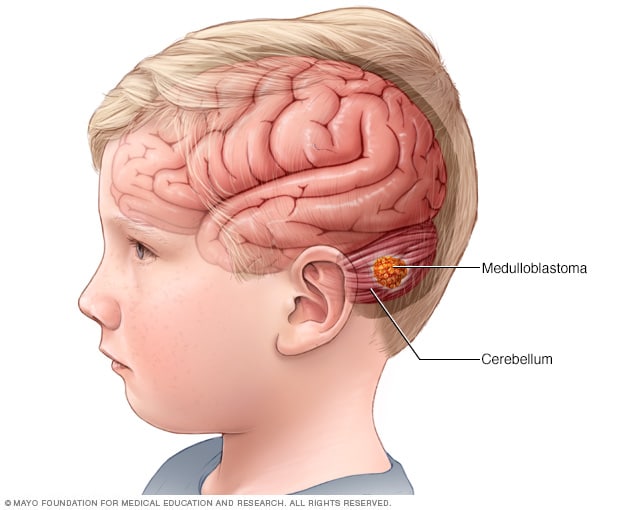

Medulloblastoma. Medulloblastoma is thought to start from a specific type of cell in the cerebellum. These cells are called cerebellar granule progenitor cells. It is most common in children and is usually cancerous, often spreading throughout the CNS. Learn about medulloblastoma in children .

Medulloblastoma

Medulloblastoma is a type of brain cancer that starts in the part of the brain called the cerebellum. Medulloblastoma is the most common type of cancerous brain tumor in children.

- Embryonal tumors. Embryonal tumors begin in cells that are left over from fetal development. The cells, called embryonal cells, stay in the brain after birth. Embryonal tumors are malignant brain tumors that happen most often in babies and young children. The most common type of embryonal tumor is medulloblastoma . It's usually located in the lower back part of the brain, called the cerebellum.

Medulloblastoma is one of the most common paediatric brain tumours 4 . Our understanding of this disease was advanced substantially by genomic studies reported in 2012. Since then, as discussed by Hovestadt et al. 8 , more genomic studies, as well as epigenomic, transcriptomic and proteomic profiling efforts, have provided new insights into medulloblastoma biology that will hopefully lead to improved diagnosis and therapy.

- Medulloblastomas usually arise in the cerebellum , most frequently in children. They are high-grade tumors, but they are usually responsive to radiation and chemotherapy .

Some types of brain tumors are more common in children than in adults. The most common types of pediatric tumors are medulloblastomas, low-grade astrocytomas (pilocytic) , ependymomas, craniopharyngiomas and brainstem gliomas .